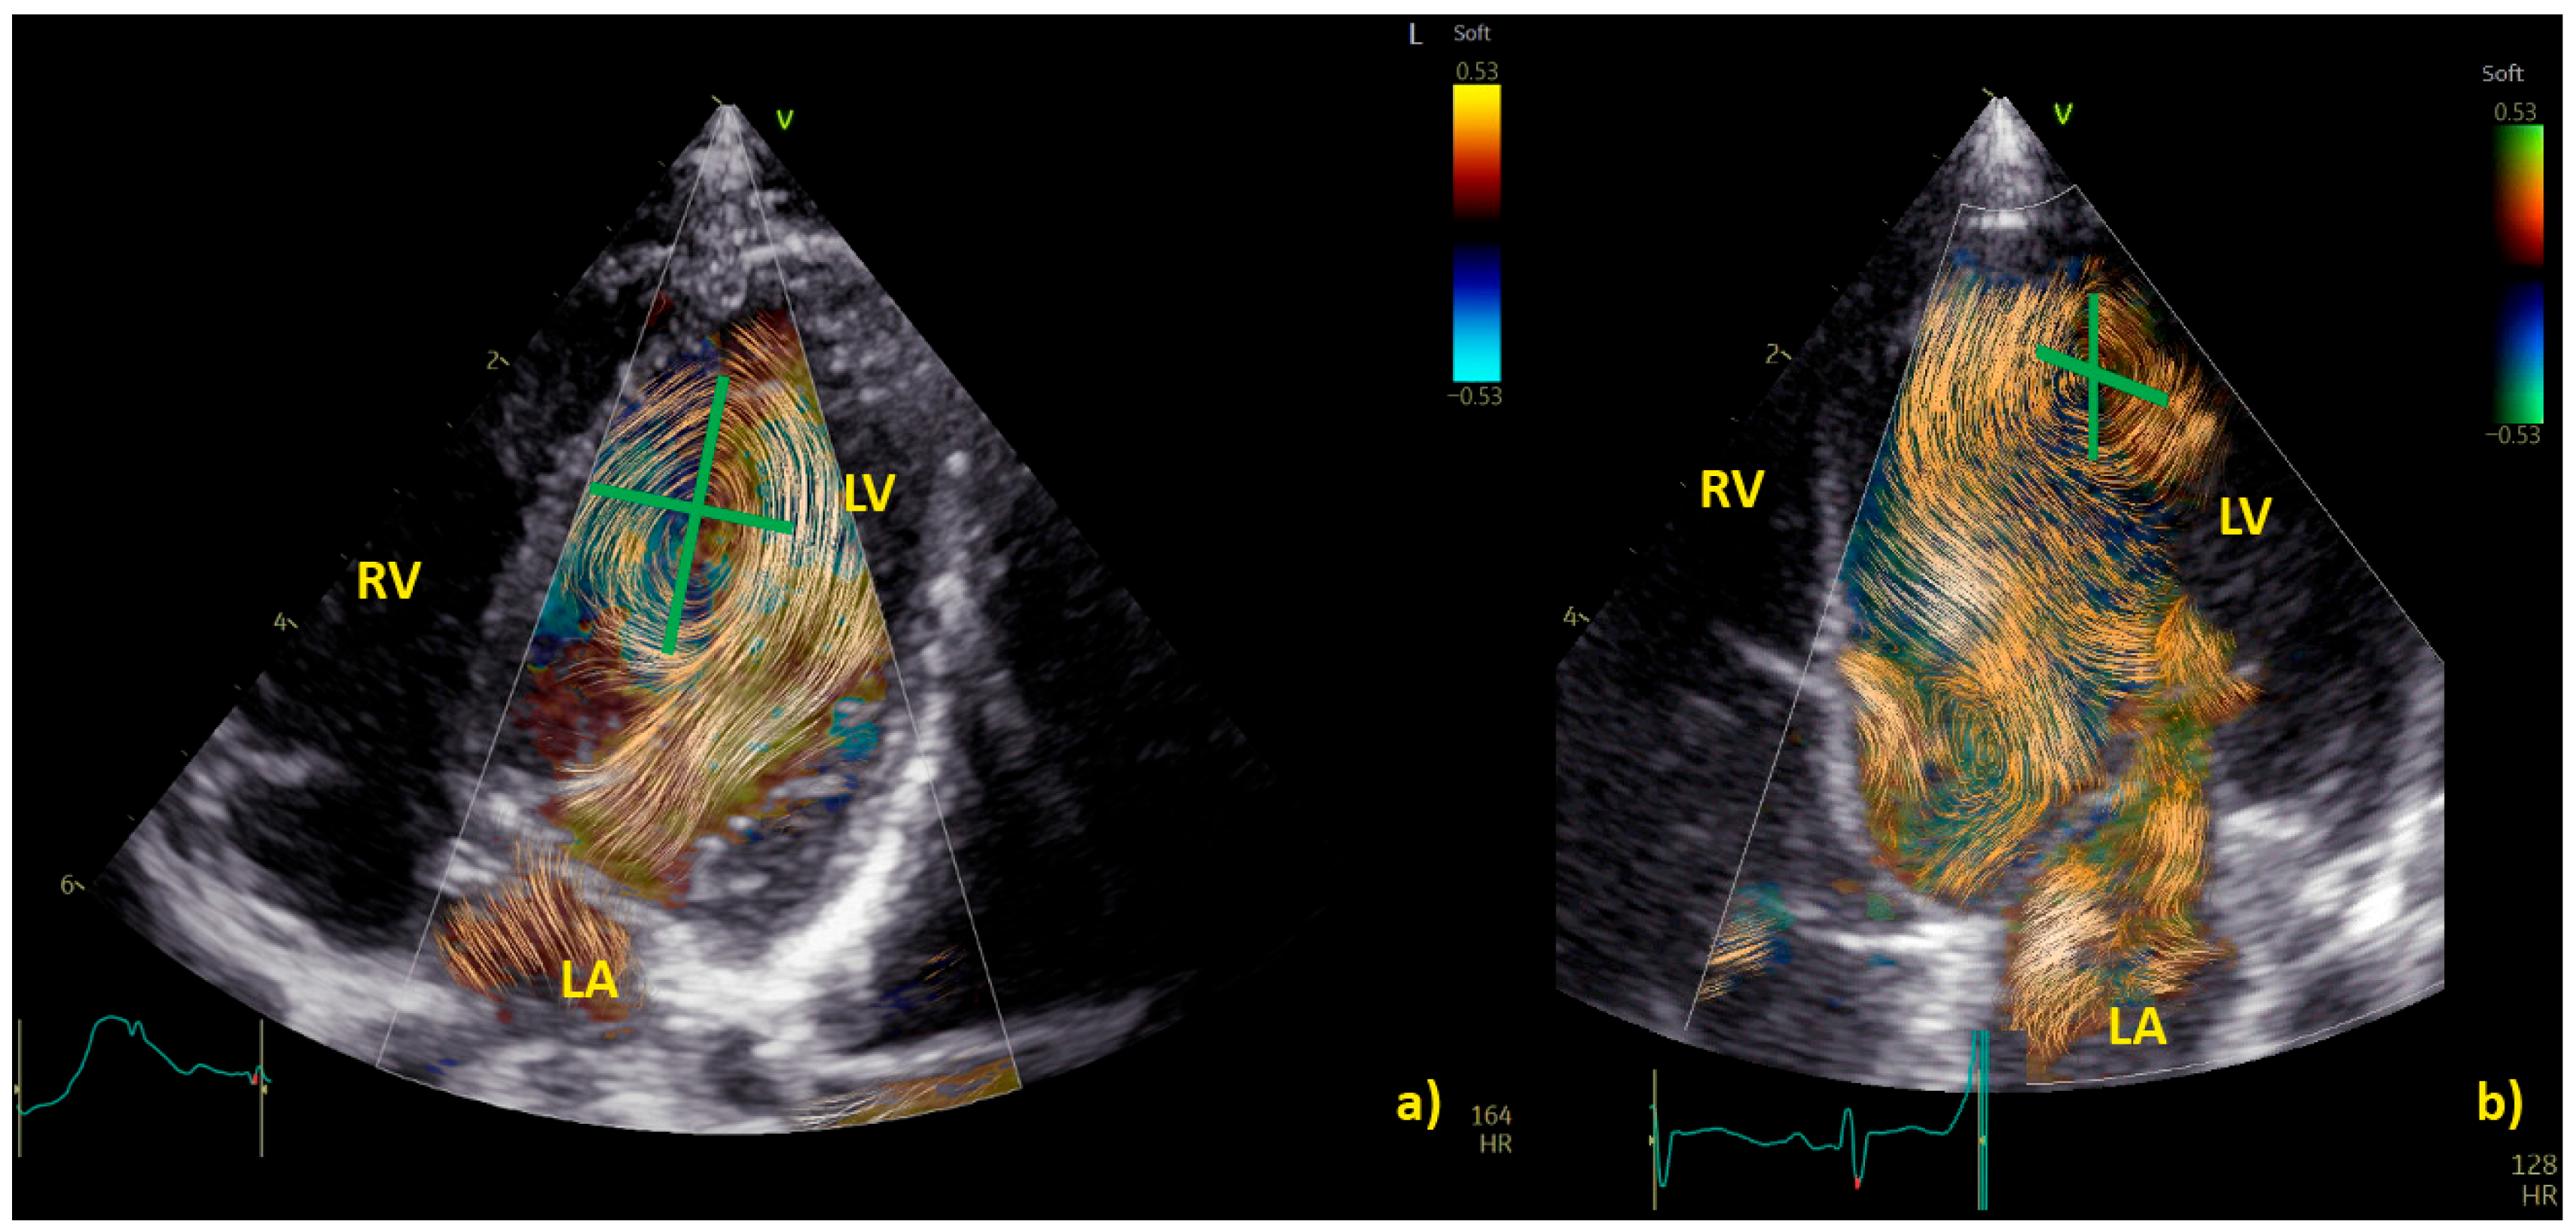

Practical examples of differences among physiological and pathological aortic vortices are provided in Figure 5. In Figure 5a, a physiological vortex is shown, while in Figure 5b, an example of a big vortex in the dilated ascending aorta of a child with a bicuspid aortic valve with moderate stenosis has been provided. The propagation of the vortex in the aortic arch in physiological condition and in a child with bicuspid aortic valve with moderate stenosis is shown in Figure 6. In the example, it appears clear that the vortex of the healthy patient (Figure 6a) occupies a smaller area than the pathological vortex and is localized on the ventral surface of the aortic arch, below the first two epi-aortic branches. On the contrary, the vortex of the child with bicuspid aortic valve valvular stenosis (Figure 6b) is located proximal to the epi-aortic branches and occupies the great part of a dilated transverse arch.

Figure 5. Vortex in the aorta of a healthy child (a) and in a patient with a bicuspid aortic valve causing moderate stenosis (b) The vortex develops at the end of diastole in both patients, but while in the healthy subject (a), physiologically we have a vortex inside the aortic root (AoRoot), in the child with bicuspid aortic valve (b), due to the stenosis, the vortex develops more distally, above the sinus-tubular junction, and it is bigger than its healthy counterpart. AoRoot = aortic root, LA = left atrium; LV = left ventricle; MV = mitral valve; RA = right atrium; RV = right ventricle.